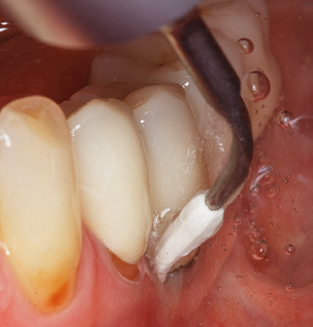

Of course, working tips for the cleaning of implant surfaces are also indispensable for SPT in patients fitted with implants. The implant cleaning attachment on the system used here is characterised by its tapered, hexagonal design. This design allows light, atraumatic penetration of the peri-implant pocket and displays a good cleaning performance (Fig. 7).